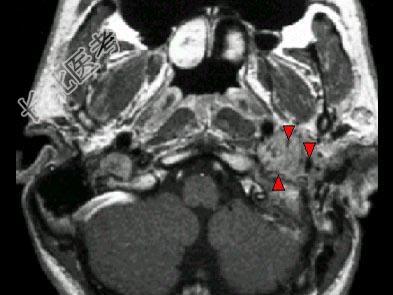

- 单项选择题男,45岁, 左侧搏动性耳鸣半年,耳镜检查透过鼓膜后下部见半膨隆紫红色肿物, CT如图,最可能的诊断是 ( )

E、颈静脉球瘤